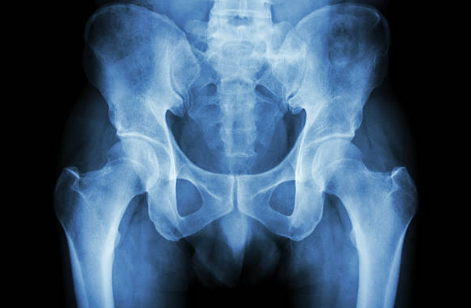

고관절 골절

고관절 골절은 특히 고령자에게 흔히 발생하며, 수술을 통해 골절 부위를 고정하거나 인공관절로 대체합니다.

고관절염

고관절의 염증이나 퇴행성 변화로 인해 통증이 심해질 경우, 인공관절 치환술을 통해 통증을 완화하고 기능을 회복할 수 있습니다.